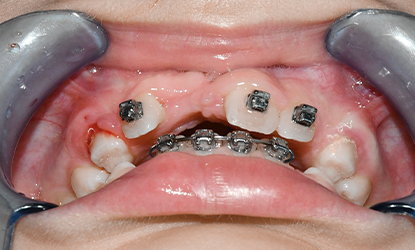

W przypadku naszej pacjentki celem leczenia było szybkie przywrócenie funkcji narządu żucia oraz trwała odbudowa brakującego zęba w przednim odcinku szczęki. Po analizie dostępnych opcji zdecydowano się na autotransplantację dolnego zęba przedtrzonowego, który znajdował się w odpowiedniej fazie rozwoju korzenia.

Utracony ząb to górny lewy siekacz przyśrodkowy (21), który został zastąpiony przez dolny ząb przedtrzonowy. Przeszczep z fragmentem kości został precyzyjnie umieszczony w przygotowanej loży kostnej.

Po stronie dawcy, czyli w miejscu usuniętego zęba przedtrzonowego, założono specjalny aparat ortodontyczny, który stabilizował przestrzeń i zapobiegał przesunięciom sąsiednich zębów.